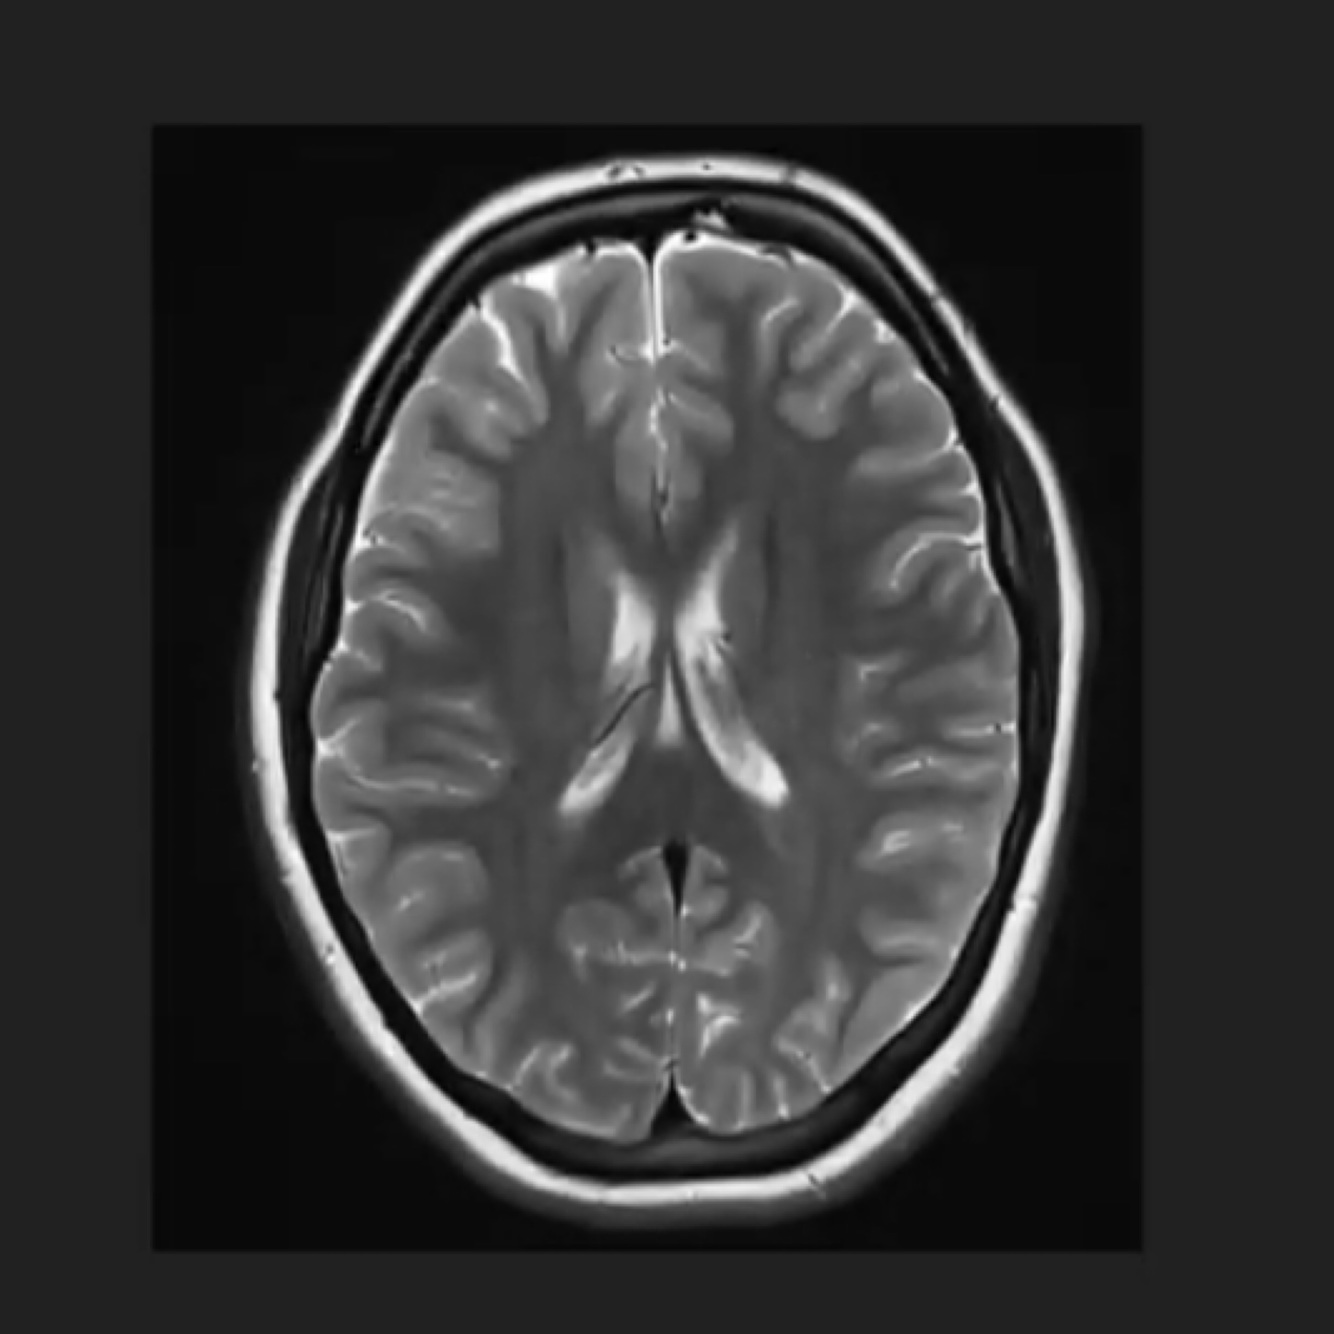

Q

Identify the CSF spaces

A

CSF between the gyri in the sulci